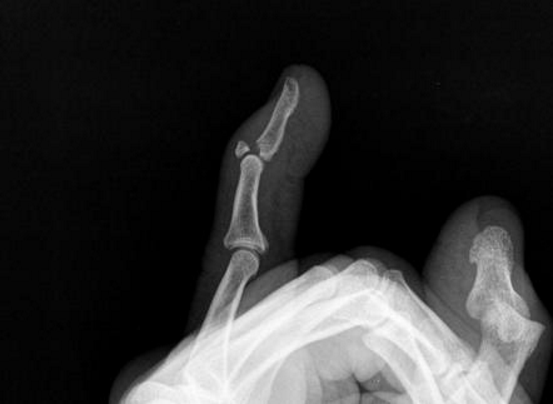

describe what ACTIVE movement would be lost in someone who has suffered mallet finger

DIP extension

describe what ACTIVE movement would be lost in someone who has suffered mallet finger and describe why this occurs

Hyperflexion injury at DIPJ avulses the extensor tendon attachment from dorsal base of distal phalanx, causing loss of DIP extension